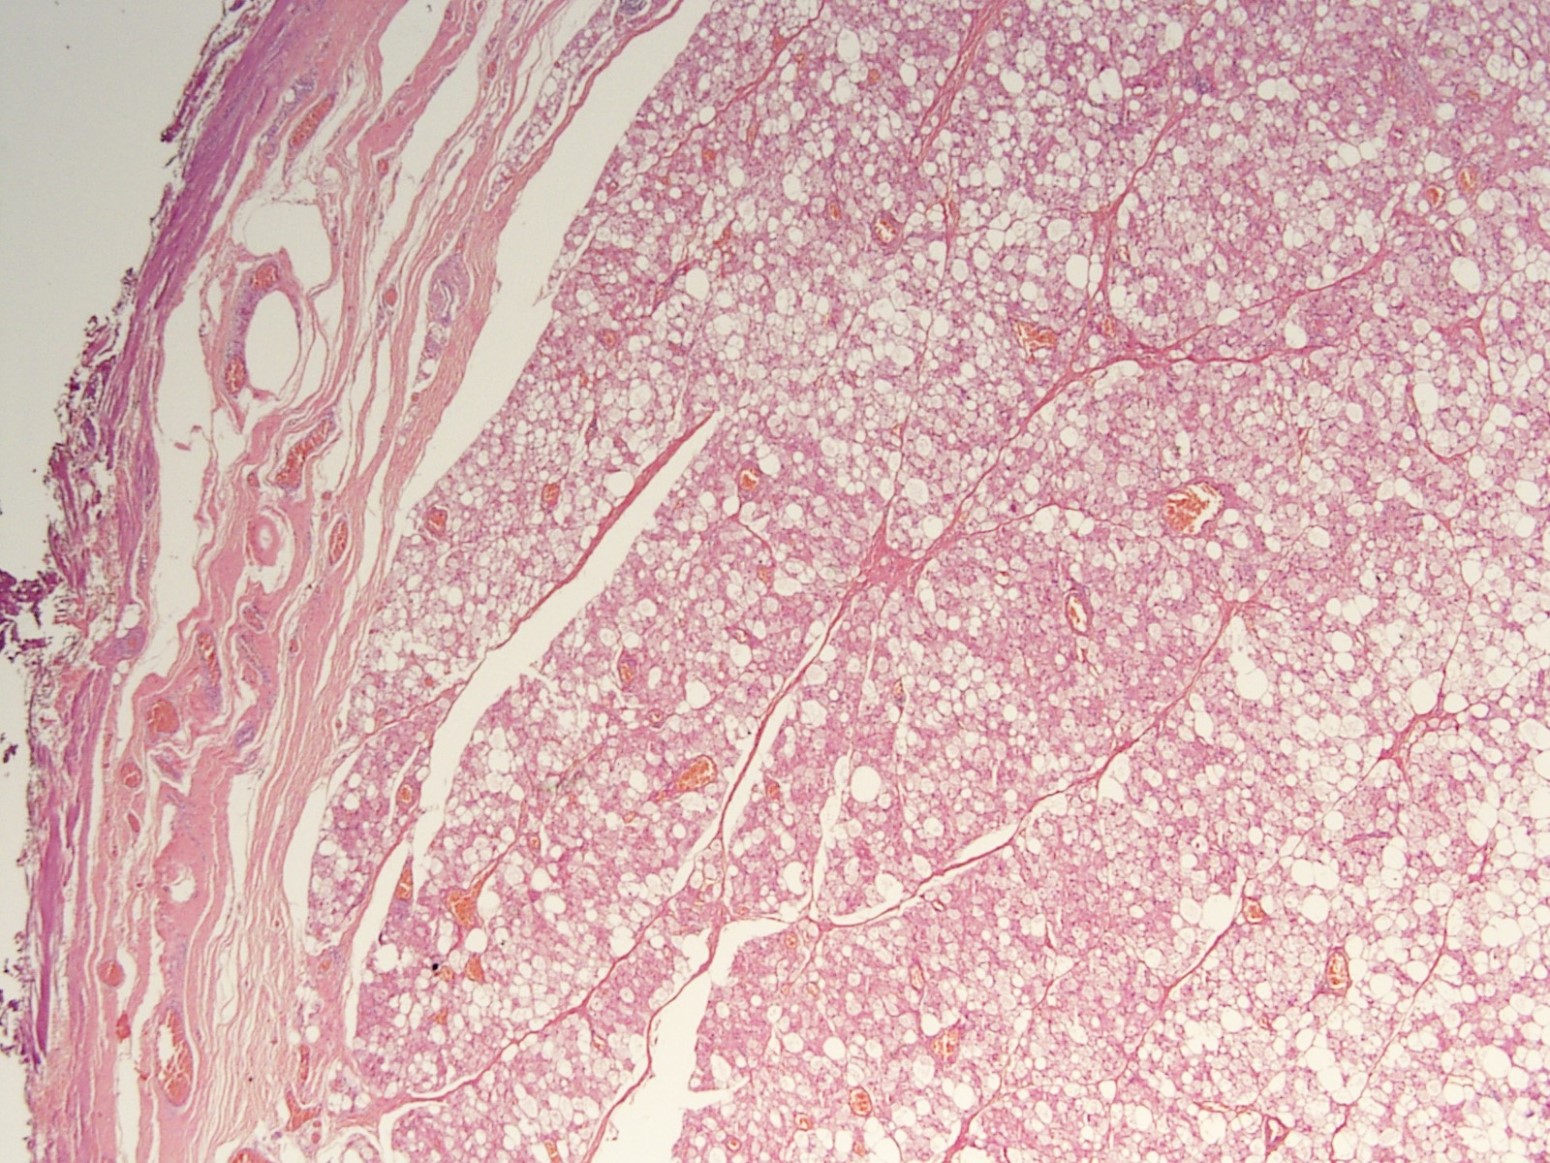

Microscopic (histologic) description

- Neoplastic lesion composed of polygonal brown fat cells with stromal cells in the background (Case Rep Oncol 2017;10:438)

- Large number of pale and eosinophilic brown fat cells with multivacuolated, eosinophilic granular cytoplasm and small central nucleus (about 70%) admixed with variable amount of univacuolated white cells (Case Rep Oncol 2017;10:438, Am J Case Rep 2020;21:e921447, J Comput Assist Tomogr 2019;43:793, J Pathol Transl Med 2017;51:499, Am J Surg Pathol 2018;42:951, Virchows Arch 2021;478:527)

- Multivacuolations resemble lipoblasts

- Morphological variations or subtypes: typical, myxoid (9%), lipoma-like (7%), spindle cell (2%), thick bundles of collagen fibers, presence of mast cells and exclusively containing brown fat cells (Case Rep Oncol 2017;10:438, Am J Case Rep 2020;21:e921447, Virchows Arch 2021;478:527)

- Cytological atypia, necrosis and mitosis is unusual (J Pathol Transl Med 2017;51:499, Am J Surg Pathol 2018;42:951, BMC Surg 2021;21:30)

Microscopic (histologic) images